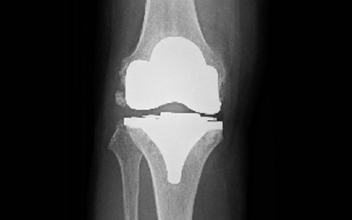

- 人工膝関節置換術

筋や腱を温存したアプローチである最小侵襲手術(MIS)を用いた手術に取り組んでおります。

この方法は従来の方法に比べて早期回復が期待できます。

通常2-3週間程度で退院となります。

人工膝関節全置換術後レントゲン